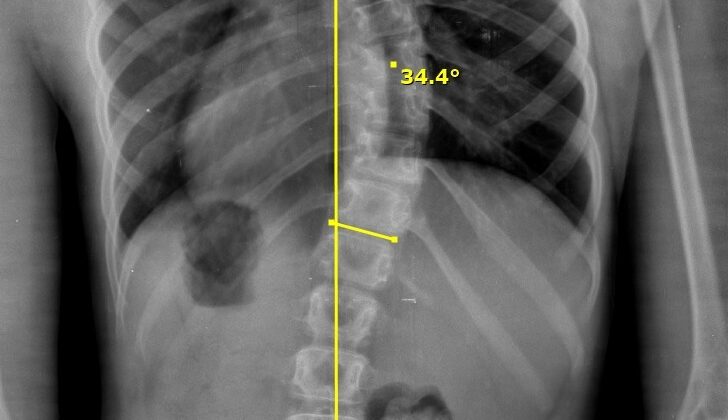

زاوية كوب هي المعيار الطبي المعتمد عالميًا لقياس درجة انحناء العمود الفقري باستخدام الأشعة السينية.

عادةً، يتم قياس زاوية كوب من خلال الأشعة السينية باتباع خطوات دقيقة، وهي:

أولًا، يحدد الطبيب أعلى فقرة في بداية الانحناء

ثم يحدد أدنى فقرة في نهاية الانحناء

بعد ذلك، يتم رسم خطوط على هاتين الفقرتين

وأخيرًا، تُحسب الزاوية الناتجة بين الخطين

وبالتالي، كلما زادت زاوية كوب، دلّ ذلك على زيادة شدة اعوجاج العمود الفقري.